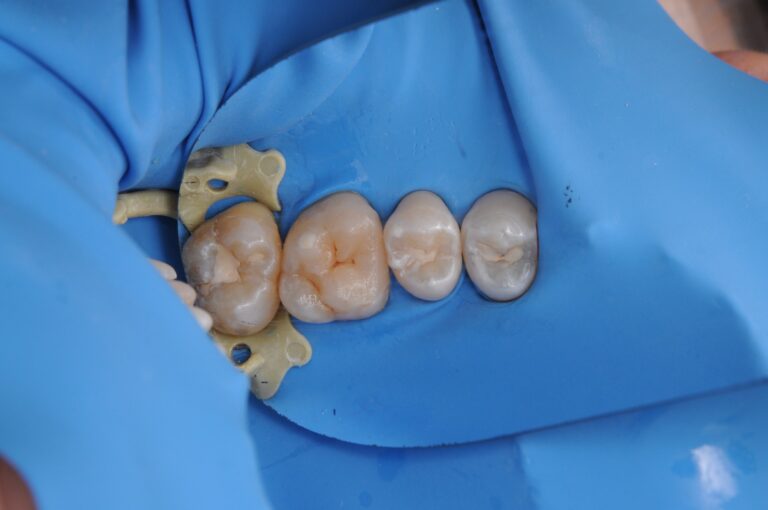

Третье фото: изоляция и чистота — залог результата

Мы изолировали зуб с помощью коффердама

и работали в максимально стерильных условиях.

Точность, сухое поле, видимость всех деталей —

всё это важно, чтобы:

• удалить весь кариес

• не повредить здоровые ткани

• добиться идеального прилегания пломбы